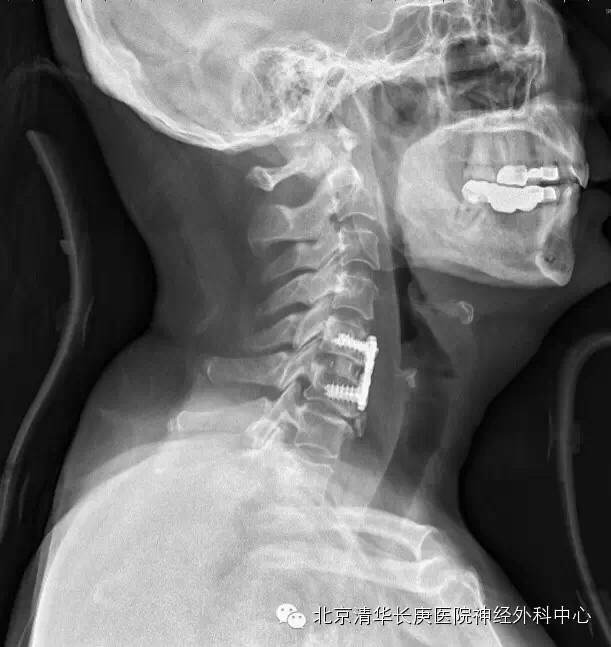

术中、后O-ARM确定:C5-6前路板固定良好